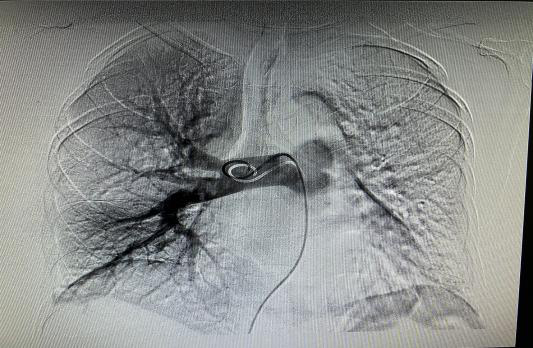

2021年1月4号晚上19点16分,患者张某,突发胸闷憋喘,我院心内科、胸外科、呼吸内科、重症监护室、介入医学科联合会诊考虑肺栓塞可能性大,急查肺动脉CTA 明确诊断。考虑患者病情重,随时有猝死的可能,介入医学科付信军主任决定急诊行下腔静脉滤器植入+肺动脉置管溶栓术抢救患者生命,给患者生的希望,术后积极溶栓抗凝治疗,现患者已较前明显好转。下图为术前术后肺动脉造影对比图: